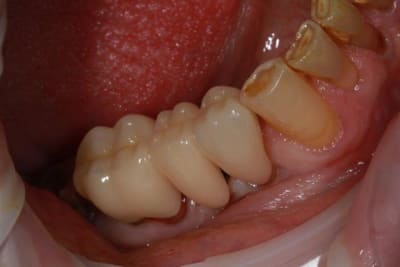

Nouveau patient, pose d'un implant il y a 2 mois....échec sans raisons particulières, douleurs et dépose.

Ce matin repose d'un nouvel implant et comme je ne veux pas prendre de risque, et que les dents adjacentes doivent être couronnées, je pose un bridge en emax press, mais scellé au ciment provisoire...

Si l'implant va bien le bridge sera déposé, coupé, et 44/46 seront collées définitivement après traitement acide et silane.

Si par hasard l'implant pose problème, dépose et bridge collé.

alors là pas du tout, le patient vient me voir pour des implants, donc je fais une étude du cas absence des molaires supérieures, couronnes mandibulaires très ancienne 45 racine cassée, 44 dévitalisée mais passablement déchaussée, donc avulsion de 45 et pose d'un implant avant de refaire les couronnes 46/47 et l'ensemble.

Échec implantaire, et oui ça arrive, même dans un cas paraissant simple.

Dépose gratuite bien sur et repose gratuite aussi, le bridge n'est pas facturé non plus, il le sera sous forme de 2 couronnes que cette fois ci l'implant fonctionne ce que j’espère, ou laissé en bridge si l'implant devait être retiré.

Le fait de scellé au ciment temporaire ne pose en principe pas de problème pour 3 à 6 mois.